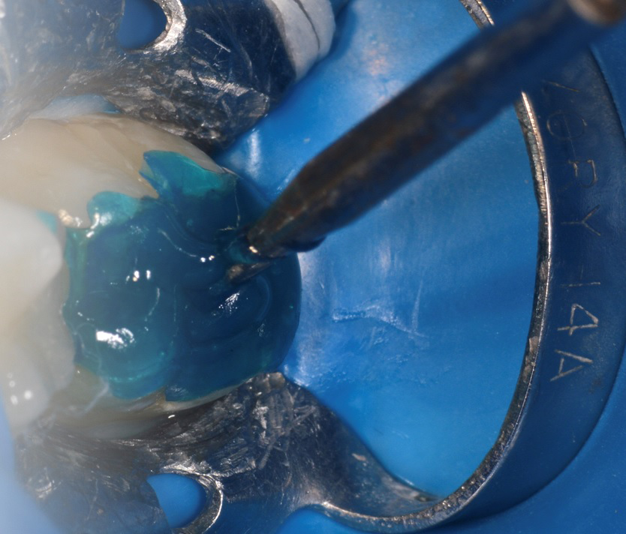

Fig. 1: A pre-operative photograph. Fig. 2: A stamp replicating the occlusal anatomy of the molar is made with a light cure flowable resin or hard setting liquid dam material. A bur is placed in the material to serve as a handle, and then it is light cured.

To create the pattern – i.e., the “stamp” – place soap or other separating medium on the occlusal surface of the tooth and flow a low viscosity resin or hard setting liquid dam material onto the surface (Fig. 2). Place a bur shaft (or microbrush) into the resin, and light cure. The bur shaft will act as the handle for the stamp (Fig. 3). Prepare the cavity in the usual manner (Fig. 4).

Fig. 3: The cured stamp with bur attached for a handle. Fig. 4: The cavity after removal of decay. Fig. 5: The mesial surface restored with ACTIVA BioACTIVE-RESTORATICE and light cured.